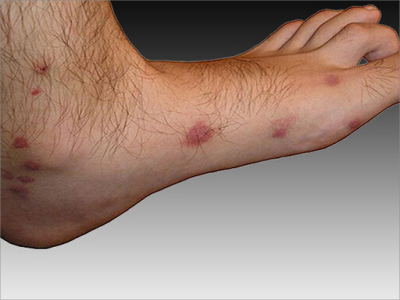

脚部

紫斑

登革热脚上有紫红色斑点图

登革热的皮肤表现主要是瘀点、瘀斑,可发生在足部,颜色呈紫红色,大小不等,形状多不规则,密集分布,为皮下出血所致,可发生融合,表面不伴有脱屑、破溃等情况。

红斑

登革热脚上出现很多暗红斑图

登革热损害发生在脚部时,表现为皮肤表面有瘀斑形成,多呈暗红色,圆形、类圆形或不规则形,大小不等,散在或密集分布,为皮下出血所致。